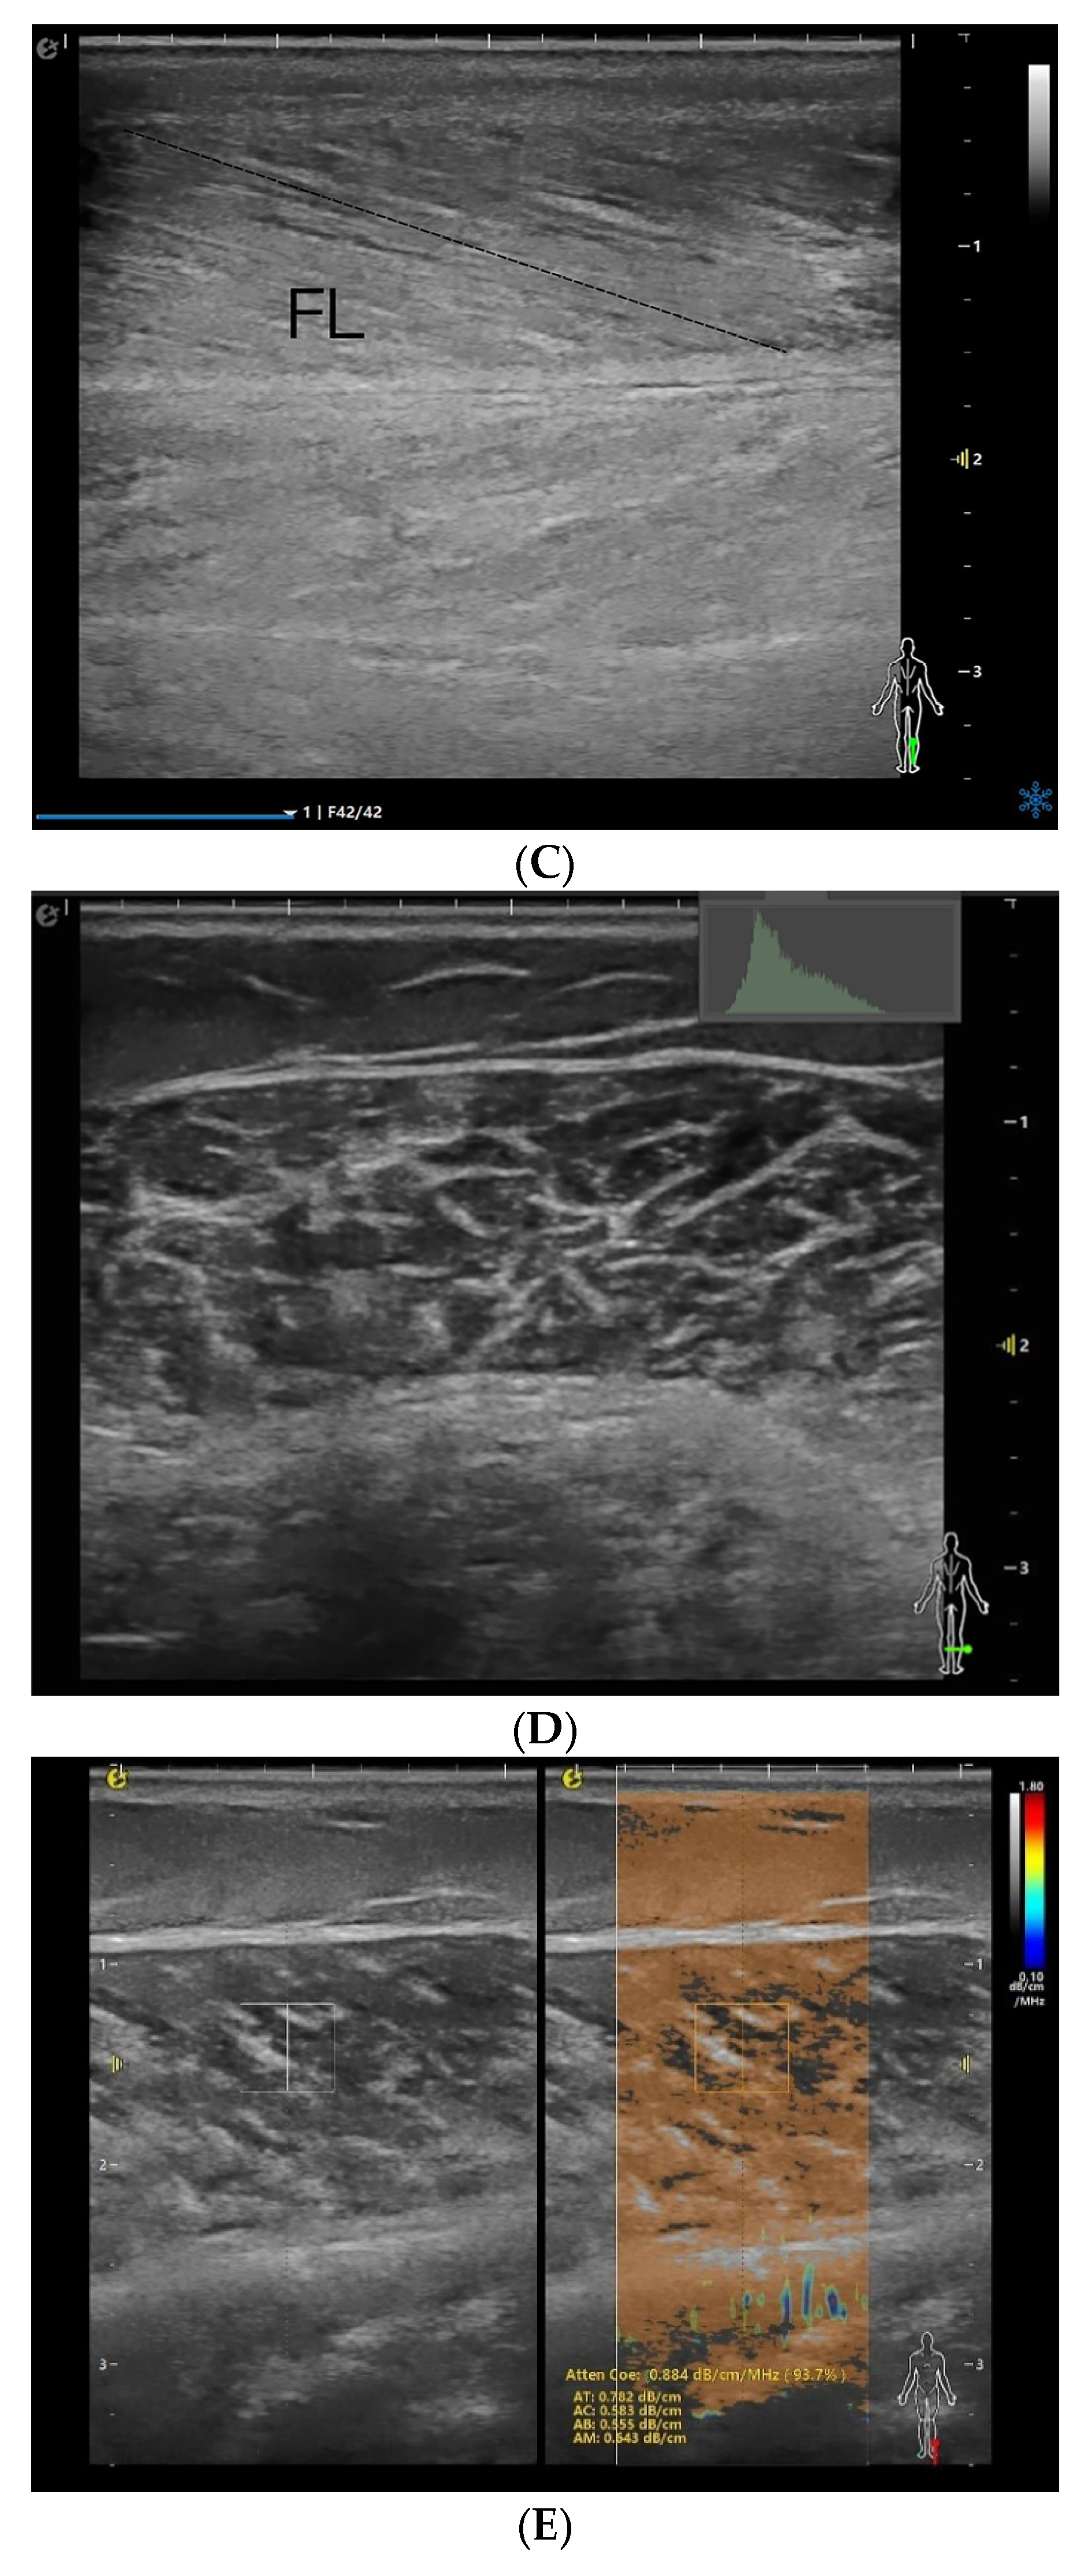

Figure 1.

MT (A), PA (B), FL (C), EI (D), and Atten Coe (E) of the medial head of the right gastrocnemius muscle in the relaxed state. MT = muscle thickness (mm); PA = pinna angle (°); FL = fascicle length (mm); Atten Coe = attenuation coefficient (dB/cm/MHz); EI = echo intensity.

On the longitudinal section, a novel RVA quantitative evaluation technique was per formed using an ultrasound system. The rectangular region of interest (ROI) was positioned at the image center, where an automated system tool for RVA quantification (4 mm diameter) was placed at the center of the ROI. The attenuation coefficient (Atten Coe) was measured on a scale ranging from 0.10 dB/cm/MHz (blue) to 1.80 dB/cm/MHz (red) (Figure 1E). All subjects were examined by the same sonographer. The above acquisitions were measured three times consecutively, and the average value was obtained. The individual values had to lie within ±5% of their mean, otherwise the set was repeated. The final value entered into the database was the arithmetic mean of the three accepted measurements, with an intra-set coefficient of variation (CV) consistently <4%, the values obtained all satisfied the homogeneity of variance.